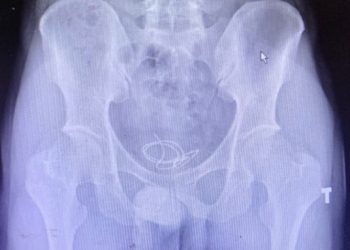

Dây headphone mắc kẹt trong bàng quang nam thanh niên

QUẢNG NINHNam thanh niên 25 tuổi nhập viện trong tình trạng đi tiểu khó và buốt, ảnh chụp X-quang phát hiện một đoạn dây đeo tai nghe (headphone) dài 20 ...